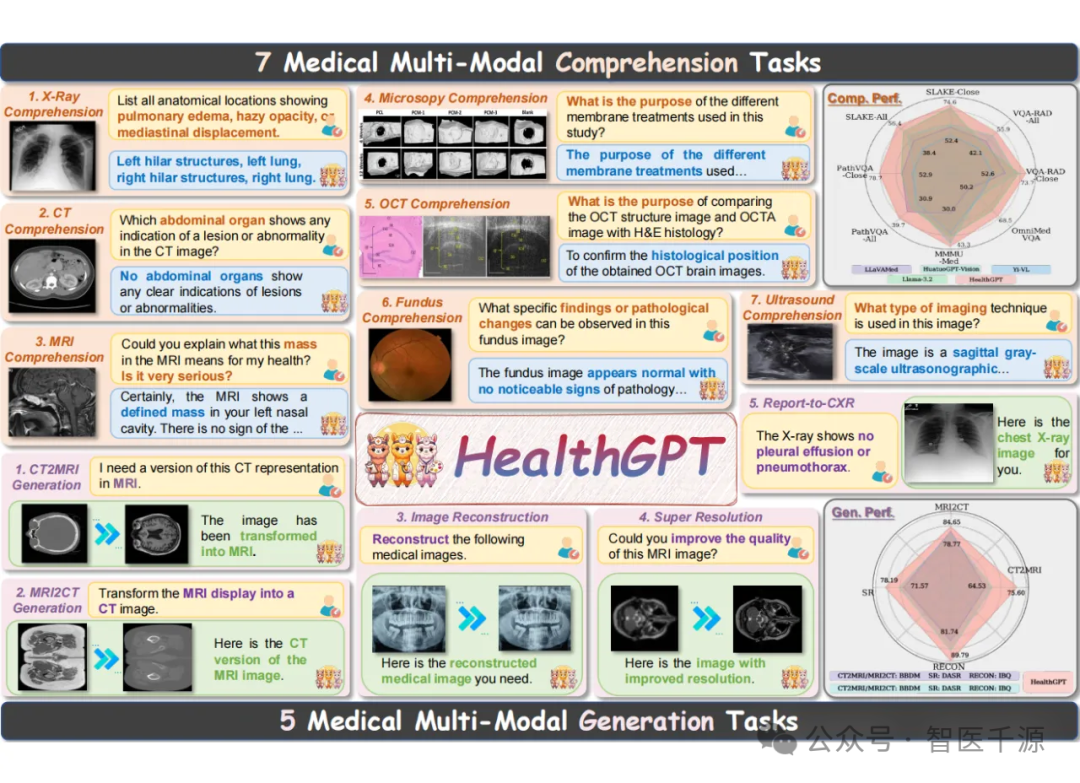

多任务支持:支持 7 种医学理解任务(如诊断问答、报告生成)和 5 种生成任务(如医学图像超分辨率、CT转MRI)。

异构知识整合:通过自回归方法将文本与图像处理无缝融合,实现跨模态医疗场景应用。

创新架构:基于大语言模型(LLM)扩展,结合视觉编码器和生成器,提升医疗图像分析与合成的精度。